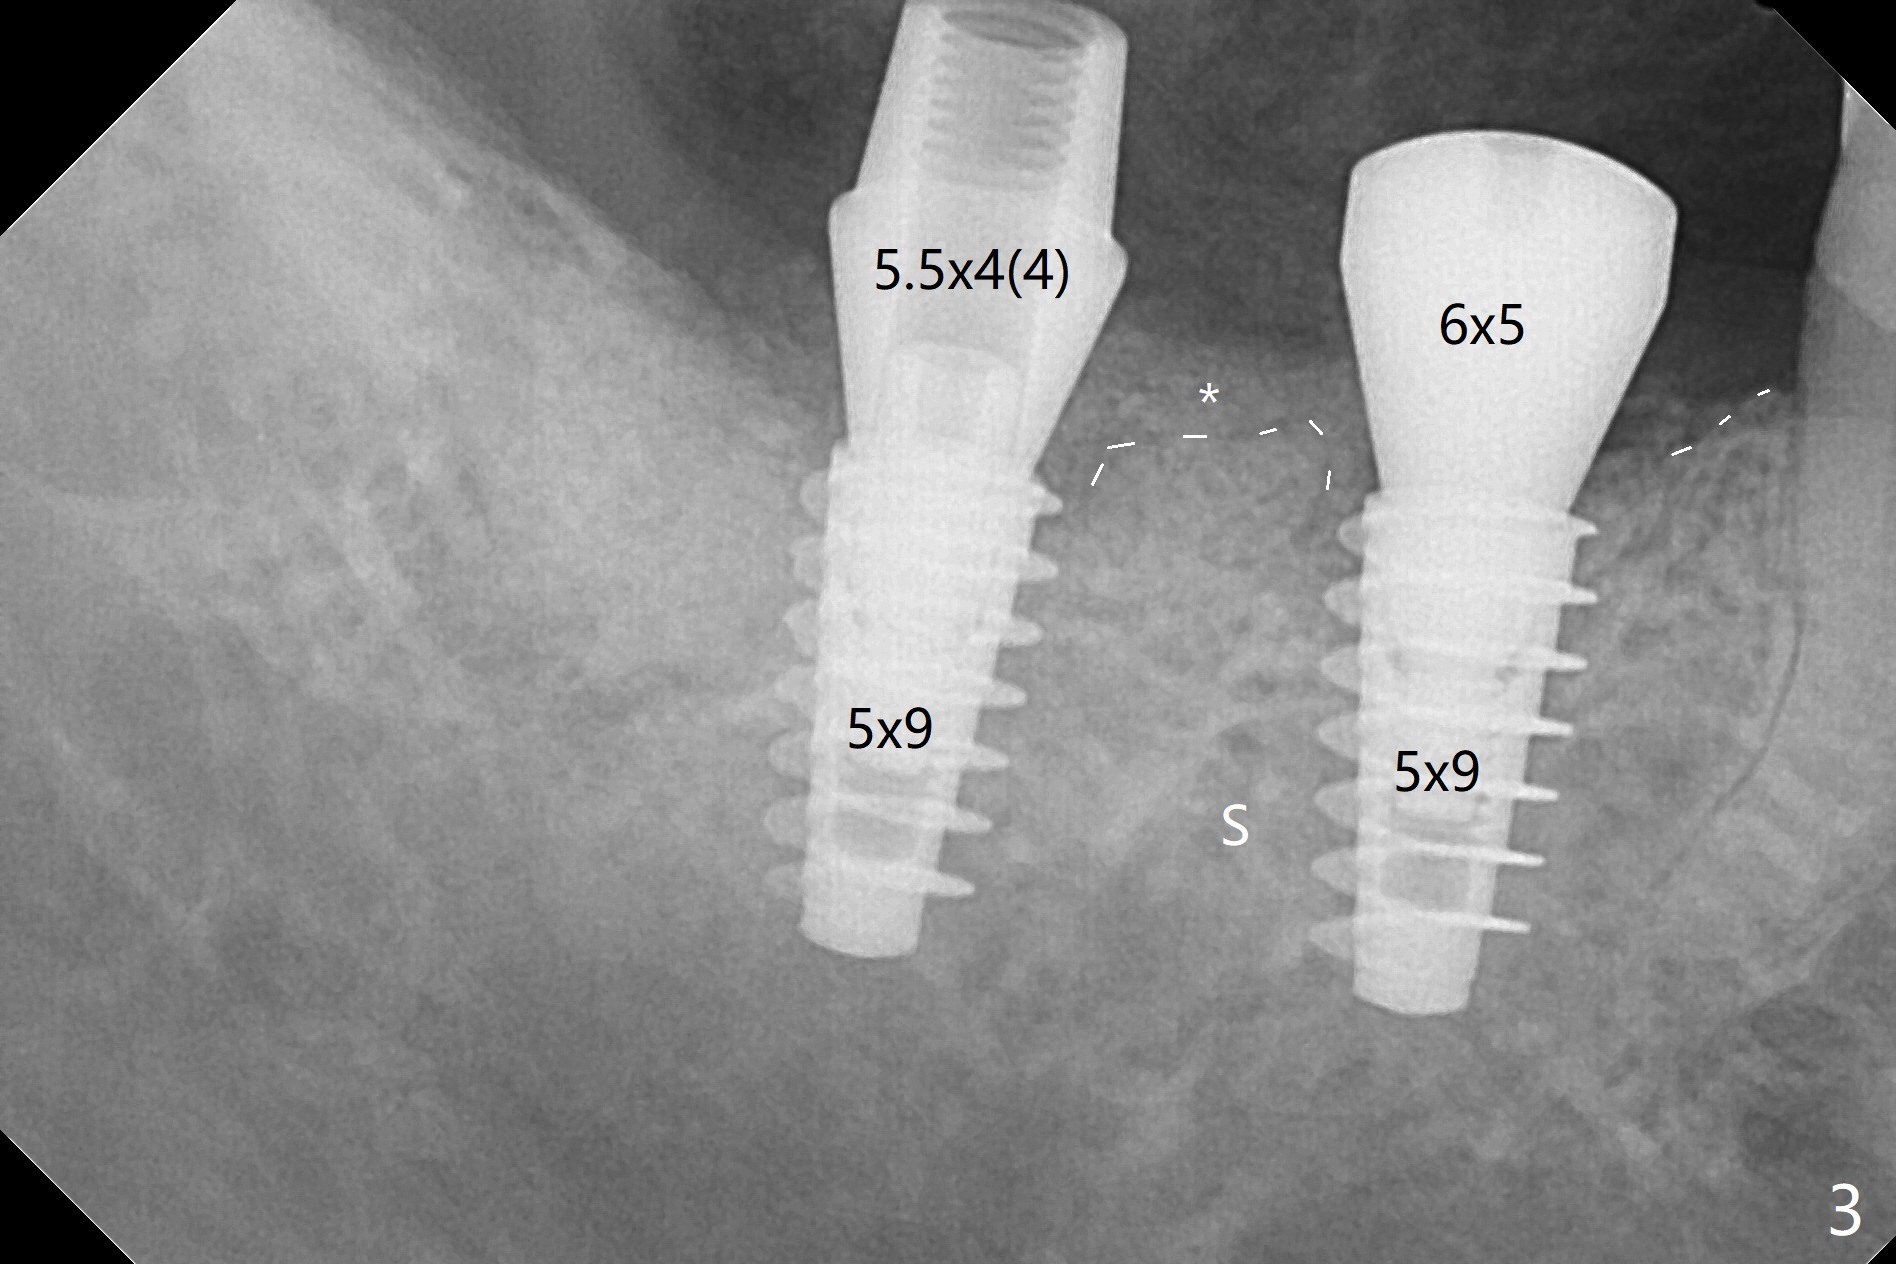

54岁男,右下6,7位点保留后7个月回来植牙,植牙床是个平面(图一),今后两个牙齿之间龈乳头一定缺乏,如何重建?放置导板,稍微使用环形钻头,在6,7植牙床上形成标记(图二),然后切开,植入植体,6扭力低,7高,所以安置愈合(6x5毫米)和修复(5.5x4(4)毫米)基台。原来导板设计把植体植入牙槽嵴(图三:白虚线)下1-2毫米,自动提高植体间牙槽嵴,接着把钻洞产生的骨粉放在后者上缘(*),由近中和远中基台固定。最后覆盖胶原膜,缝合(图四)。原来导板需要切除的角化龈保留住了(图四:7B,7L)。放入修复基台目的是利用它的高度固定牙周敷料。术后3个月7牙槽窝愈合(位点保存后10个月,图五:*),植体间牙槽嵴仍旧高(箭头),6放置修复基台,准备做临时牙冠。右上7反合,需要做局部矫正(图六)。病人非常感激术后三个月制作的临时牙冠(连体)。术后五个月对临时牙冠进行修改:6牙合面垫高(图七:*),这样上下7牙合面分开,上7颊侧放置矫正器,下7牙圈(舌侧有cleat),两者之间安置橡皮筋,上7就可以自由往舌侧移动。术后8.5个月全景片和CT显示植体种植牙槽嵴下(图八至十),这也是重建龈乳头基础。